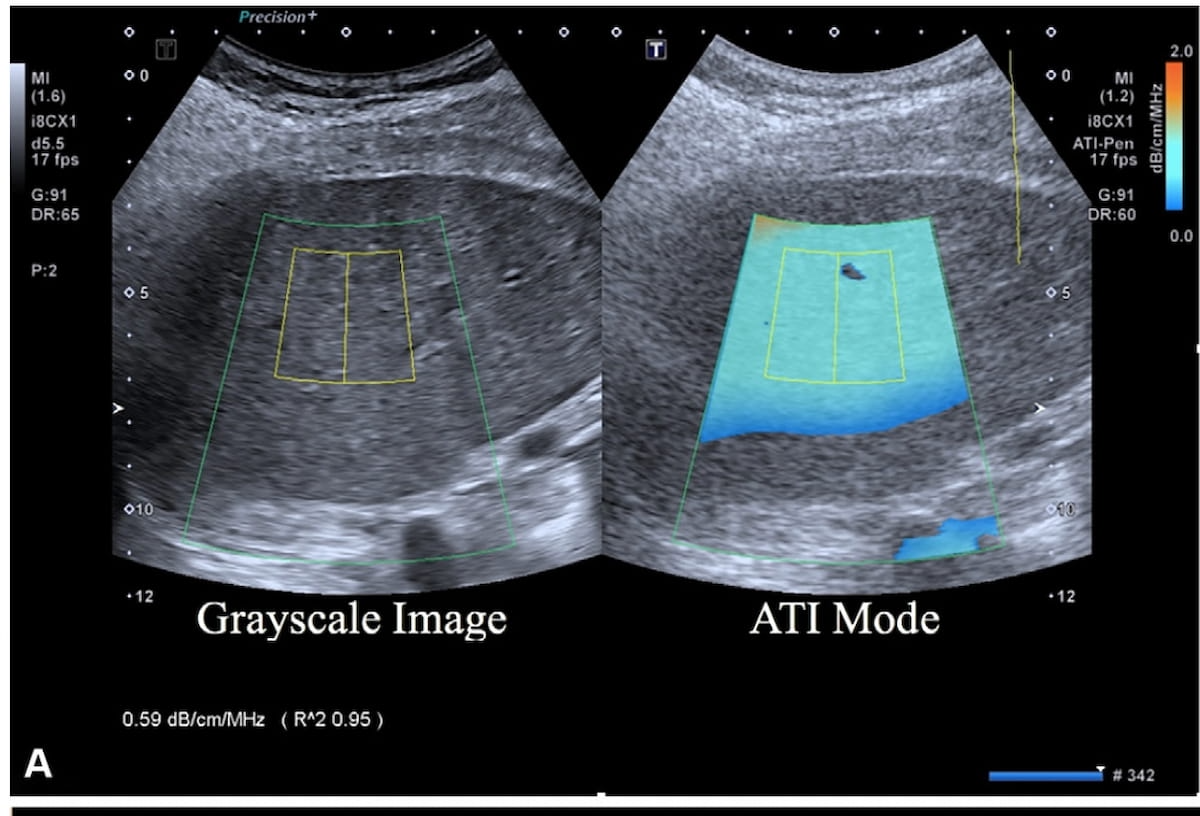

What does the current evidence reveal for four FDA-cleared AI software modalities for breast ultrasound? Leading researchers review the study findings in a recently published literature review.